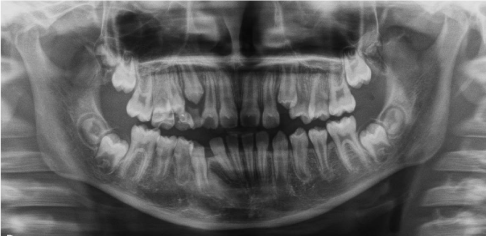

Marsupialization and biopsy was performed and a lingual arch is applied to maintain the space for erupting teeth. After three, six and nine months from the marsupialization ortopanthomography was done til to the eruption of the involved tooth (Figures 13-15).

Figure 13 Case 4. Three months after the marsupialization

Figure 14 Case 4. Six months after the marsupialization

Figure 15 Case 4. After nine months the involved teeth were erupted